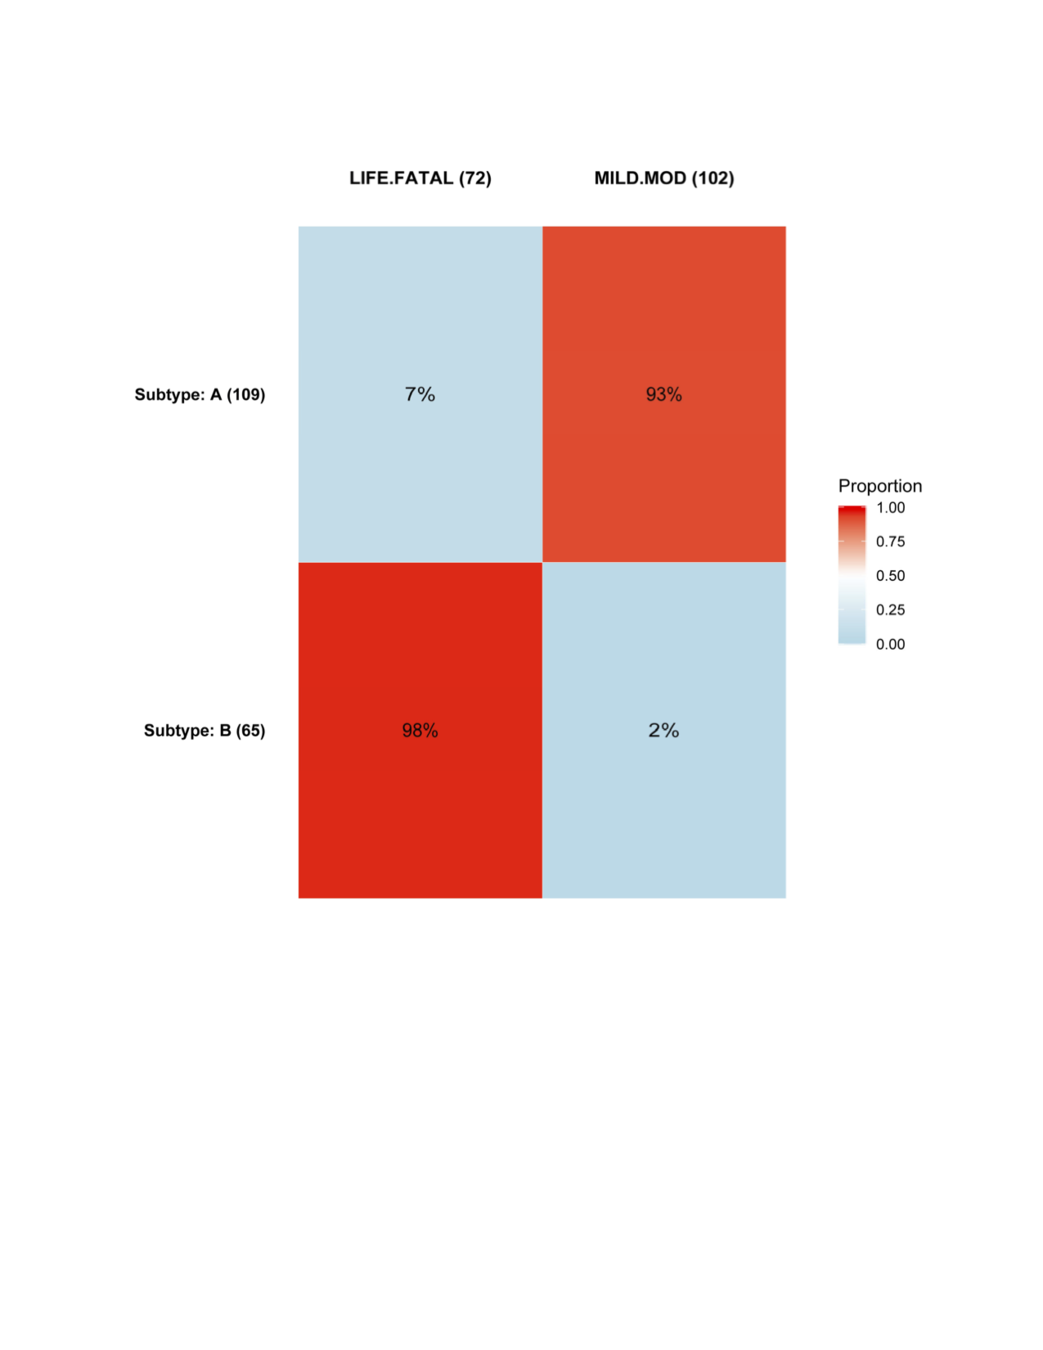

Anonymous drug 1

Received "accelerated approval"

Subtype response based on baseline characteristics

Anonymous Drug 1

Was found to be effective for a certain type of cancer.

Ran into problems with severe toxicity events (449 toxicities out of 607).

Goal was to find subtypes least (or most) likely to have toxicity events.